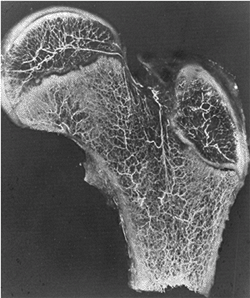

![]() |

Figure 26.3 Pathoanatomy of SCFE is demonstrated.A: No displacement is seen. B:

Rotation of the proximal femoral neck, with the femoral head (which is anchored in the acetabulum) posterior relative to the femoral neck. C: Progressive external rotation, with progressive posterior relation of the femoral head to the femoral neck. D: Proximal migration of the femoral neck due to the markedly posterior relation of the femoral head to the femoral neck. (From Morrissy RT. Principles of in situ fixation in chronic slipped capital femoral epiphysis. Instr Course Lect 1989;38:257–262, with permission.) |